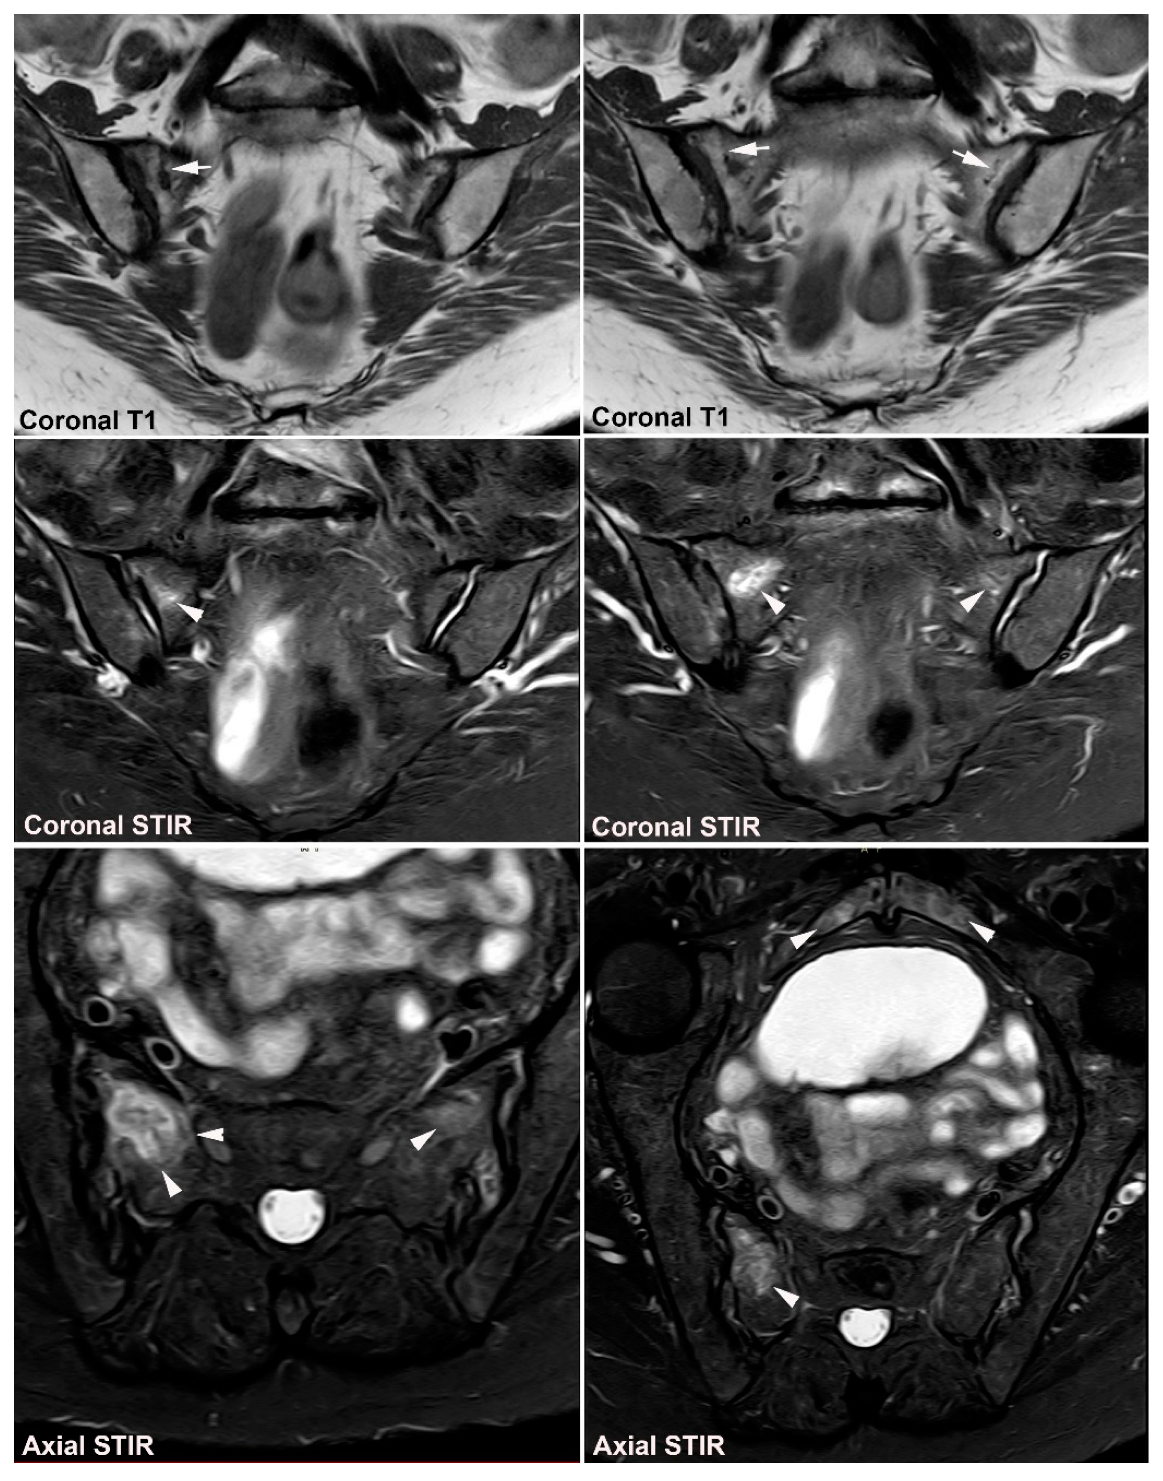

9. Infectious Sacroiliitis

10.1. Sacral Stress Fracture

10.2. Sacral Insufficiency Fracture